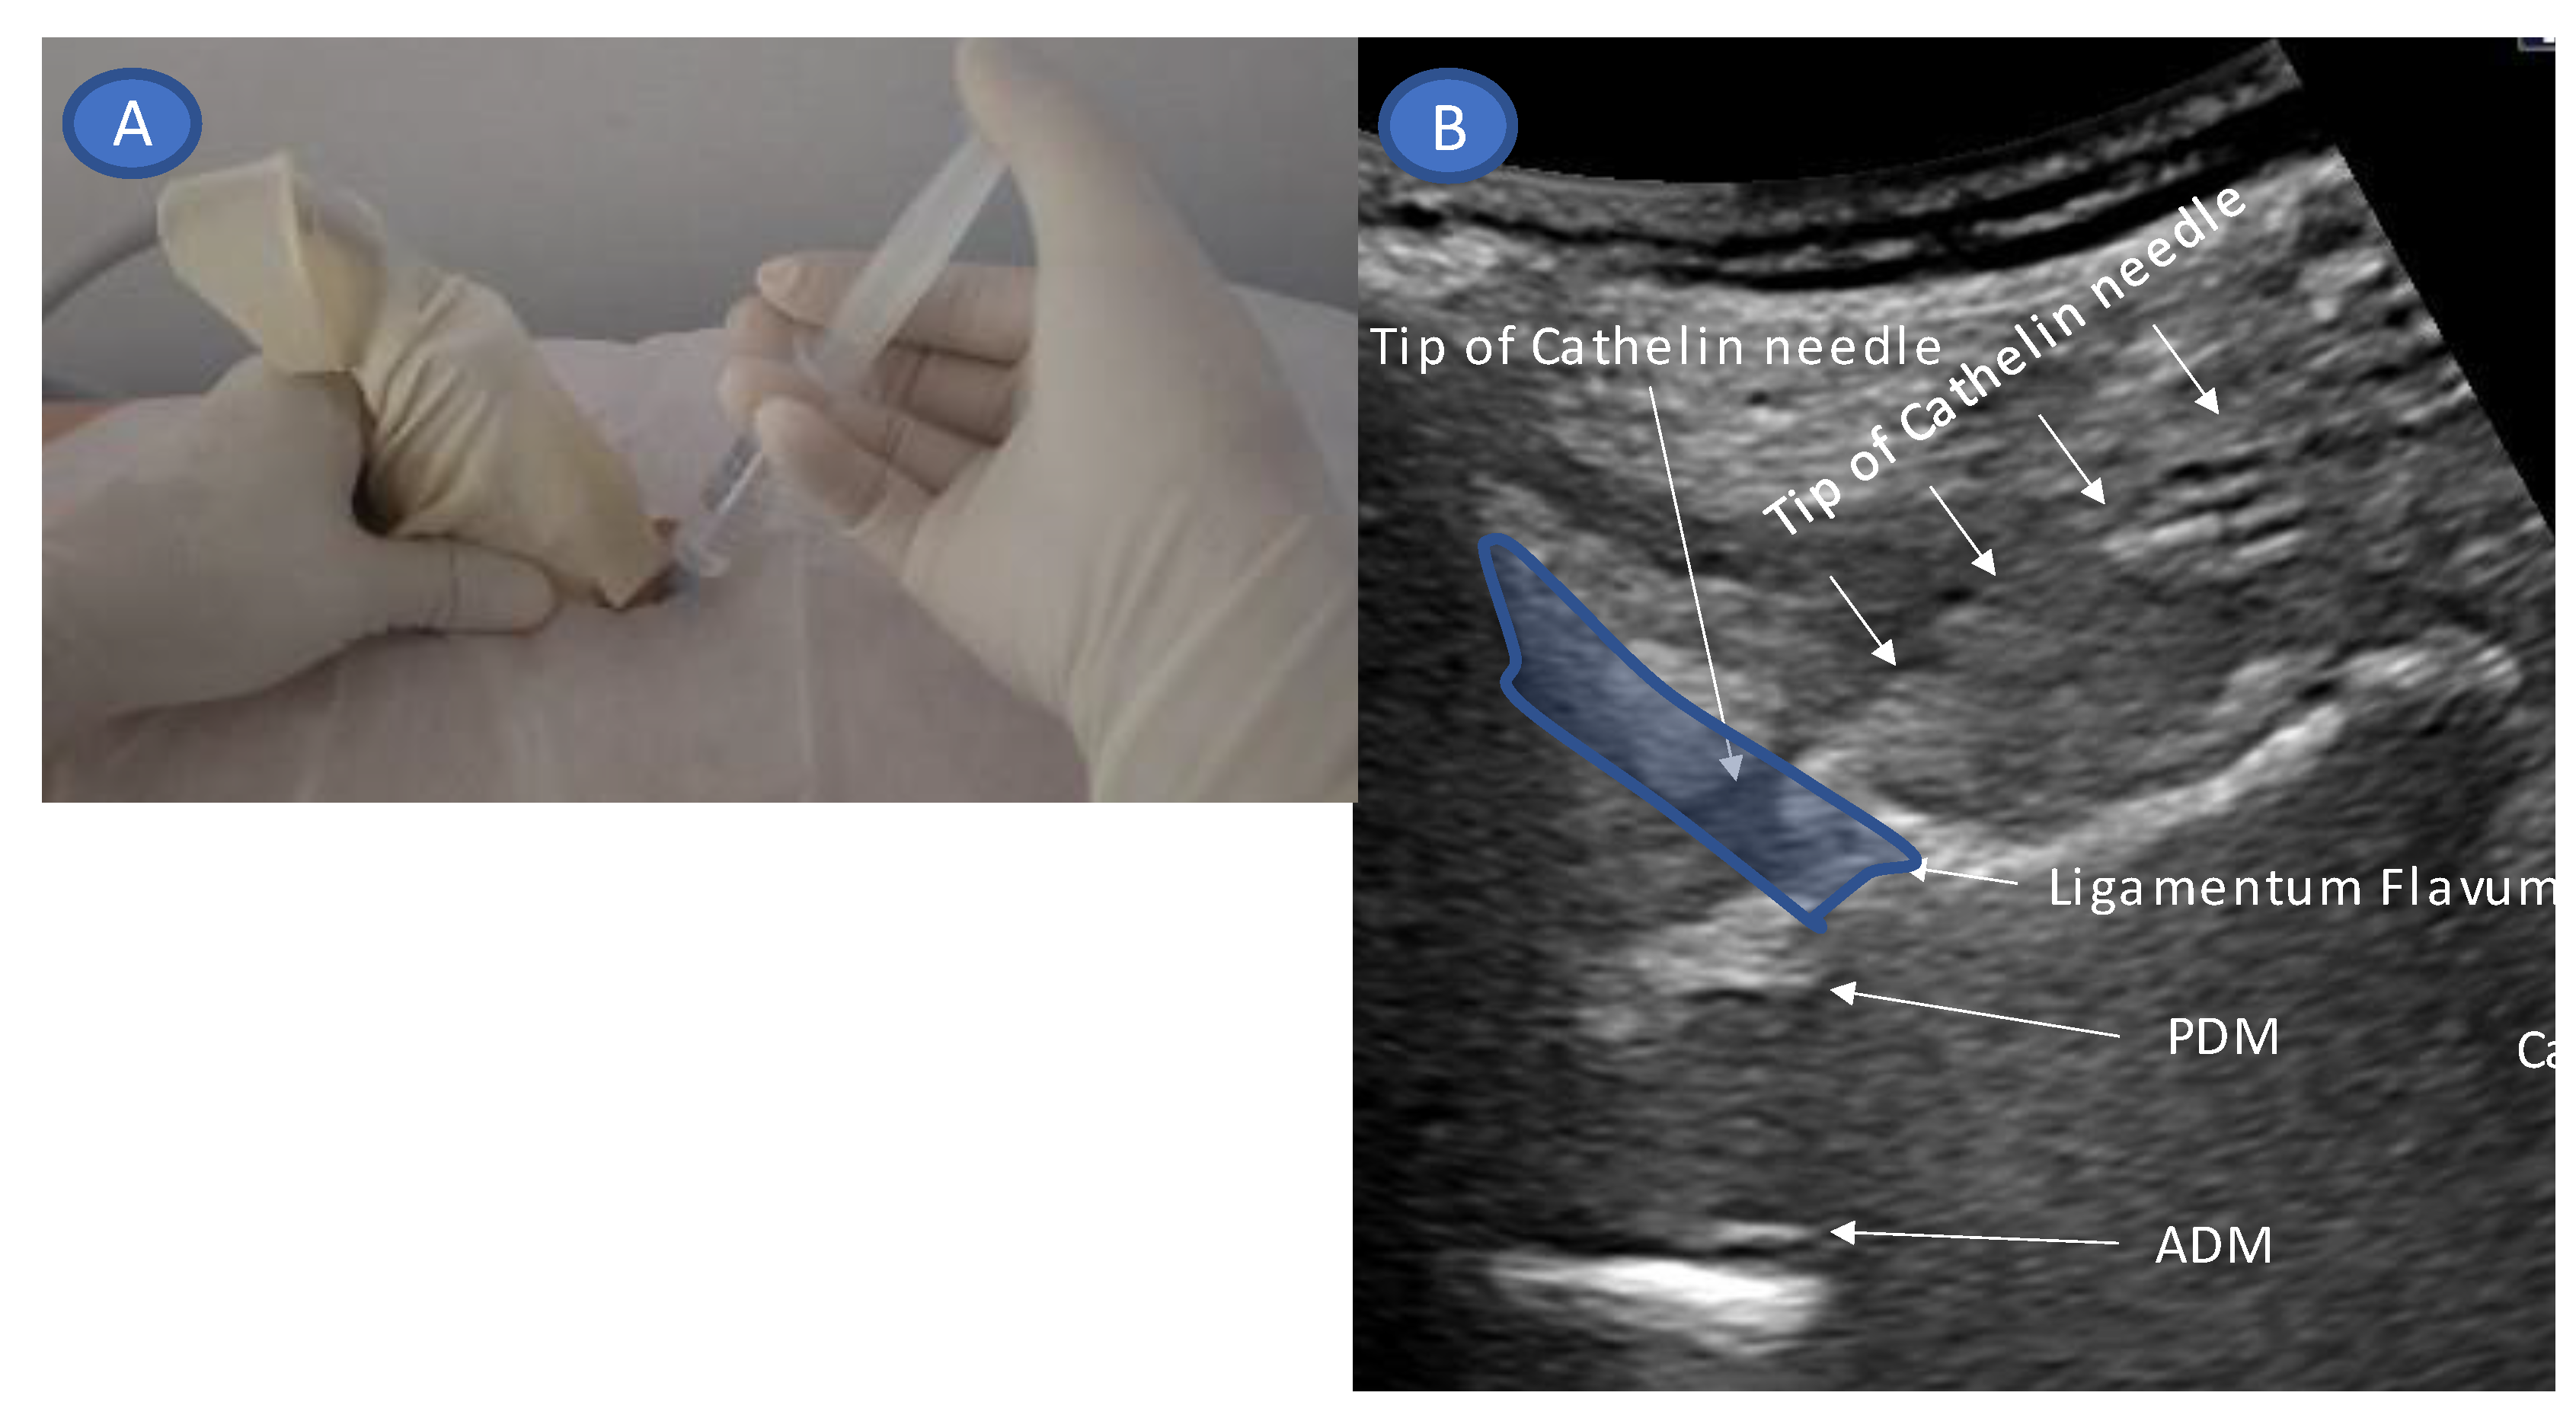

- Guide the needle into the ligamentum flavum.

- Advance the needle to the depth where resistance disappears (LOR).

- Confirm that the site of LOR is the epidural space.

- Confirm that the drug solution is appropriately distributed into the epidural space.

- Accurate needle tip guidance into the ligamentum flavum behind the epidural fat layer;

- Palpation of resistance by finger sense during ligamentum flavum insertion while confirming with sonography;

- Confirmation of the position of the needle tip in the ligamentum flavum;

- Tracing the spread of the drug in the epidural space using SMI during the injection.